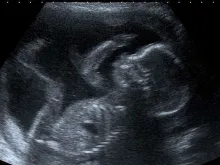

Montana, EUA, não pode mais exigir consentimento dos pais para menores fazerem abortos

A Suprema Corte de Montana, EUA, invalidou uma lei estadual que exigia consentimento dos pais para menores fazerem abortos, alegando... Leia mais

Pedem abertura de sindicância contra médico que realizou aborto em menina de 10 anos

O Movimento Legislação e Vida entrou com um pedido de abertura de sindicância no Conselho Regional de Medicina de Pernambuco... Leia mais